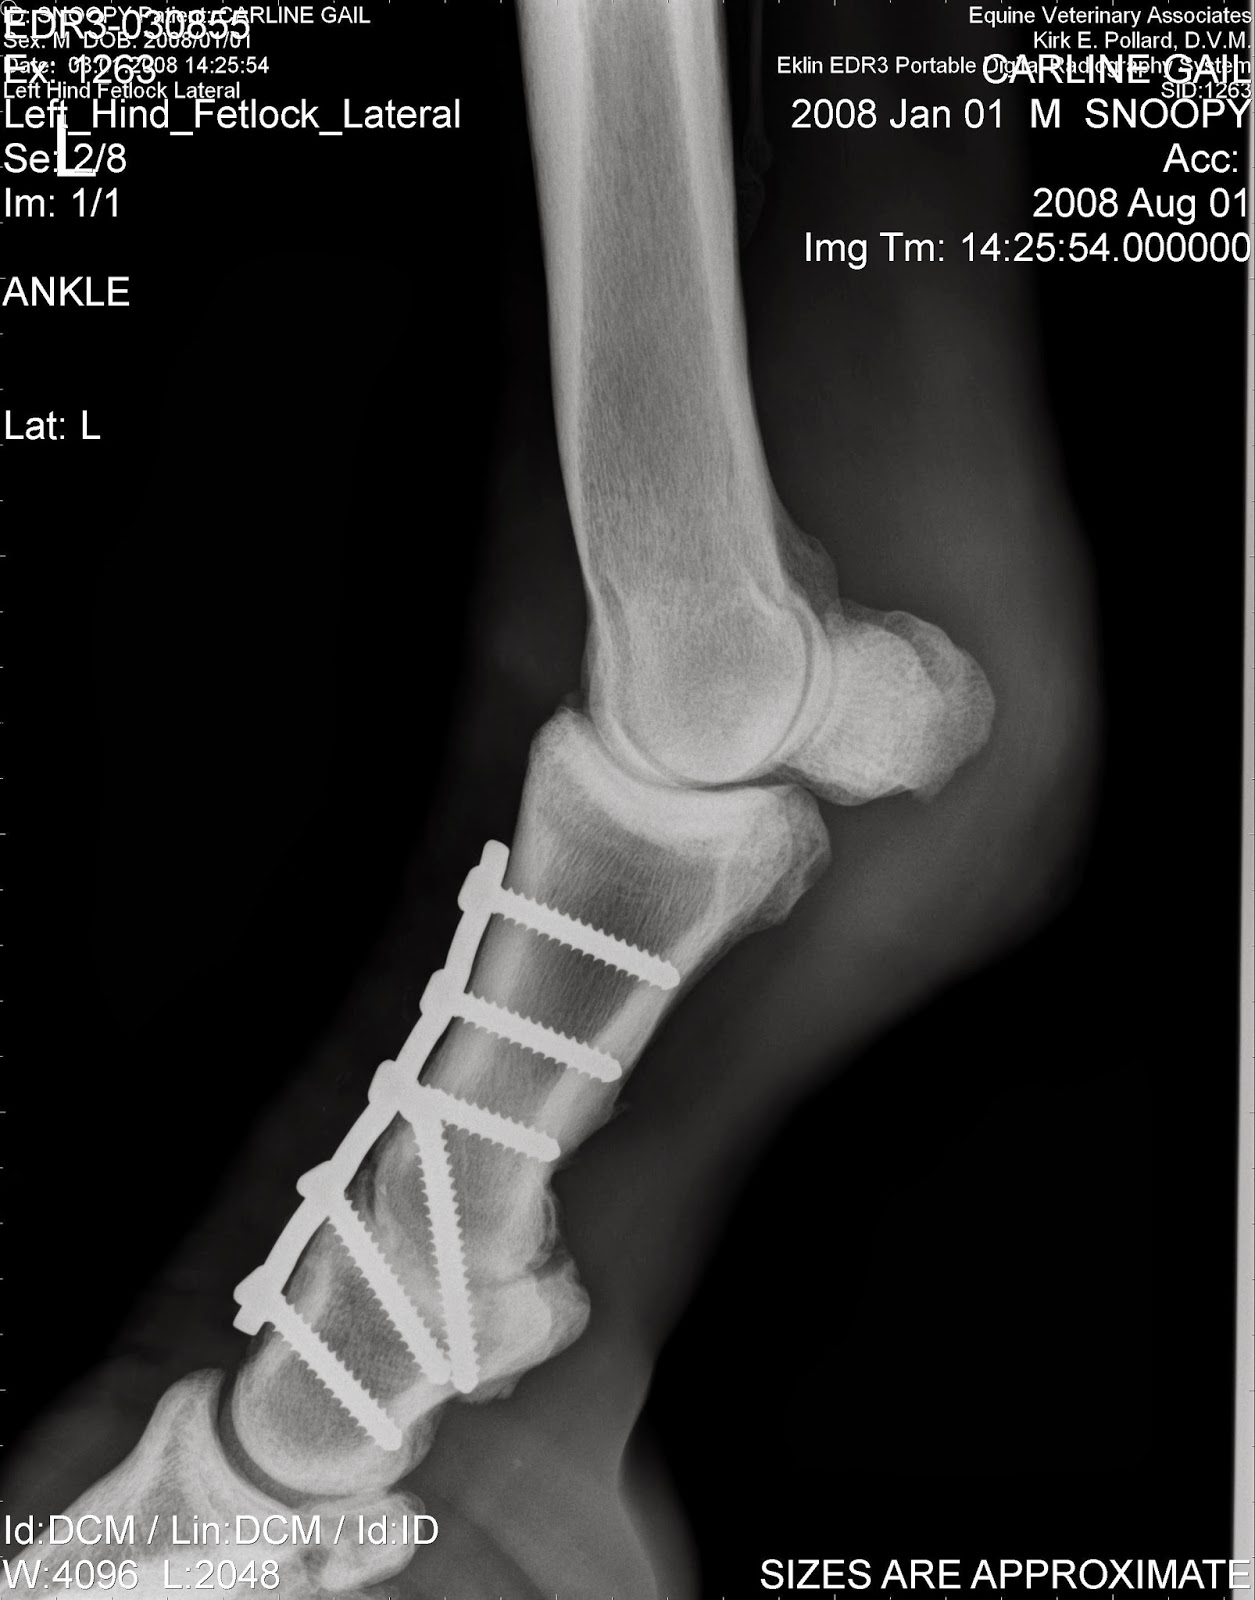

Pdf | fractures of the proximal sesamoid bones (psbs) range in severity from simple to complex and comminuted and diagnosis and management of proximal sesamoid bone fractures in the horse. Proximal sesamoid bones are located in the lower limbs of the horse and are part of the metacarpophalangeal.

Horses with apical sesamoid fractures have a good prognosis for returning to racing following arthroscopic removal of the fragment. Size and shape of apical sesamoid fractures does not appear to. When this is completely across the bone, the broken fragments are forced asunder by the.

Fractures of one of the sesamoid bones is often the cause of lameness in race horses.

[sesamoid bone fractures in trotting horses. The apical fragment was removed in 80 of the horses. Sustained a sesamoid fracture during the may 4 pat day mile stakes presented by lg & e and ku he seemed ok (following the may 4 race) but i knew something was wrong. This is a vital time getting the patient in a. In horses with continued athletic expectations, acute fractures are preferably removed arthroscopically unless they. Dr richard blake discusses the first 3 months of treatment for a sesamoid fracture under the big toe joint. Fracture in horses including diagnosis and symptoms, pathogenesis, prevention, treatment, prognosis and more. Trout, the gelding's breeder/owner/trainer, said. Due to the great stress placed on the fetlock during fast exercise. Sesamoid injuries in horses can be difficult to repair and even catastrophic; Sesamoid fractures are common injuries to race horses and are usually due as a result from depending on the location of the fracture and the age and use of the horse, these injuries can be. All information is peer reviewed. Millionaire shotgun kowboy has been retired because of a sesamoid fracture, c.r. Fracture of the sesamoids results in sudden lameness, but in degree varying with the nature of the fracture. These fractures may occur due to a violent strain or may result from a traumatism. Horses with apical sesamoid fractures have a good prognosis for returning to racing following arthroscopic removal of the fragment. [sesamoid bone fractures in trotting horses.